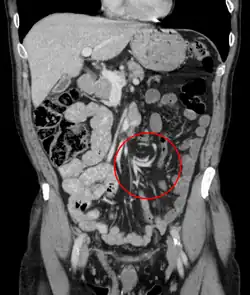

| Coronal CT of the abdomen, demonstrating a volvulus as indicated by twisting of the bowel stock | |

Coffee bean sign in a person with sigmoid volvulus -

Coronal view of sigmoid volvulus with "whirlpool sign" -